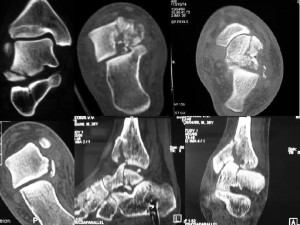

Схожие симптомы с артрозом будут тому причиной. При появлении первых подозрений, врач обычно отправляет пациента на рентгеновское обследование, а оно не в состоянии обнаружить некроз на ранних стадиях. На рентгеновских снимках можно выявить разрушения только на второй или третей стадиях заболевания. Поэтому лечащий врач, который будет руководствоваться только рентгеновским снимком, может упустить возможность пациента выздороветь, не прибегая к хирургическому вмешательству.

Вовремя выявить некроз кости, возможно, только с помощью двух томографий. Помогут распознать болезнь в самом начале, магнитно-резонансное и компьютерное обследование. Именно подобные методики помогут своевременно выявить болезнь и избежать хирургической операции.